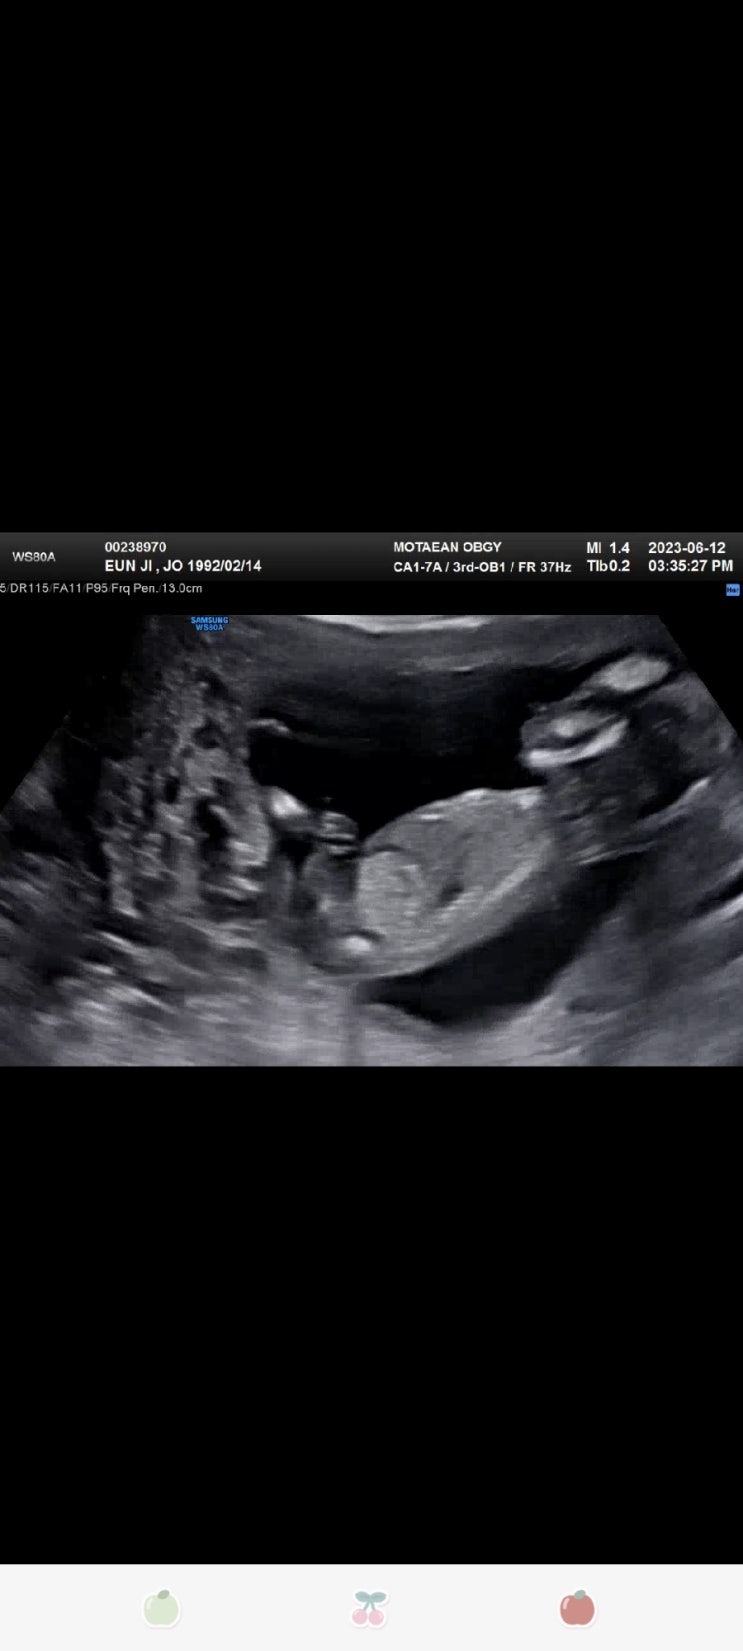

포근이는 아들래미 확정♡

배는 벌써 이만큼이나 나옴 다른 13주차 임산부보다 많이 나온듯 나 복부지방... 많니..? 그덕에 허리+환도...